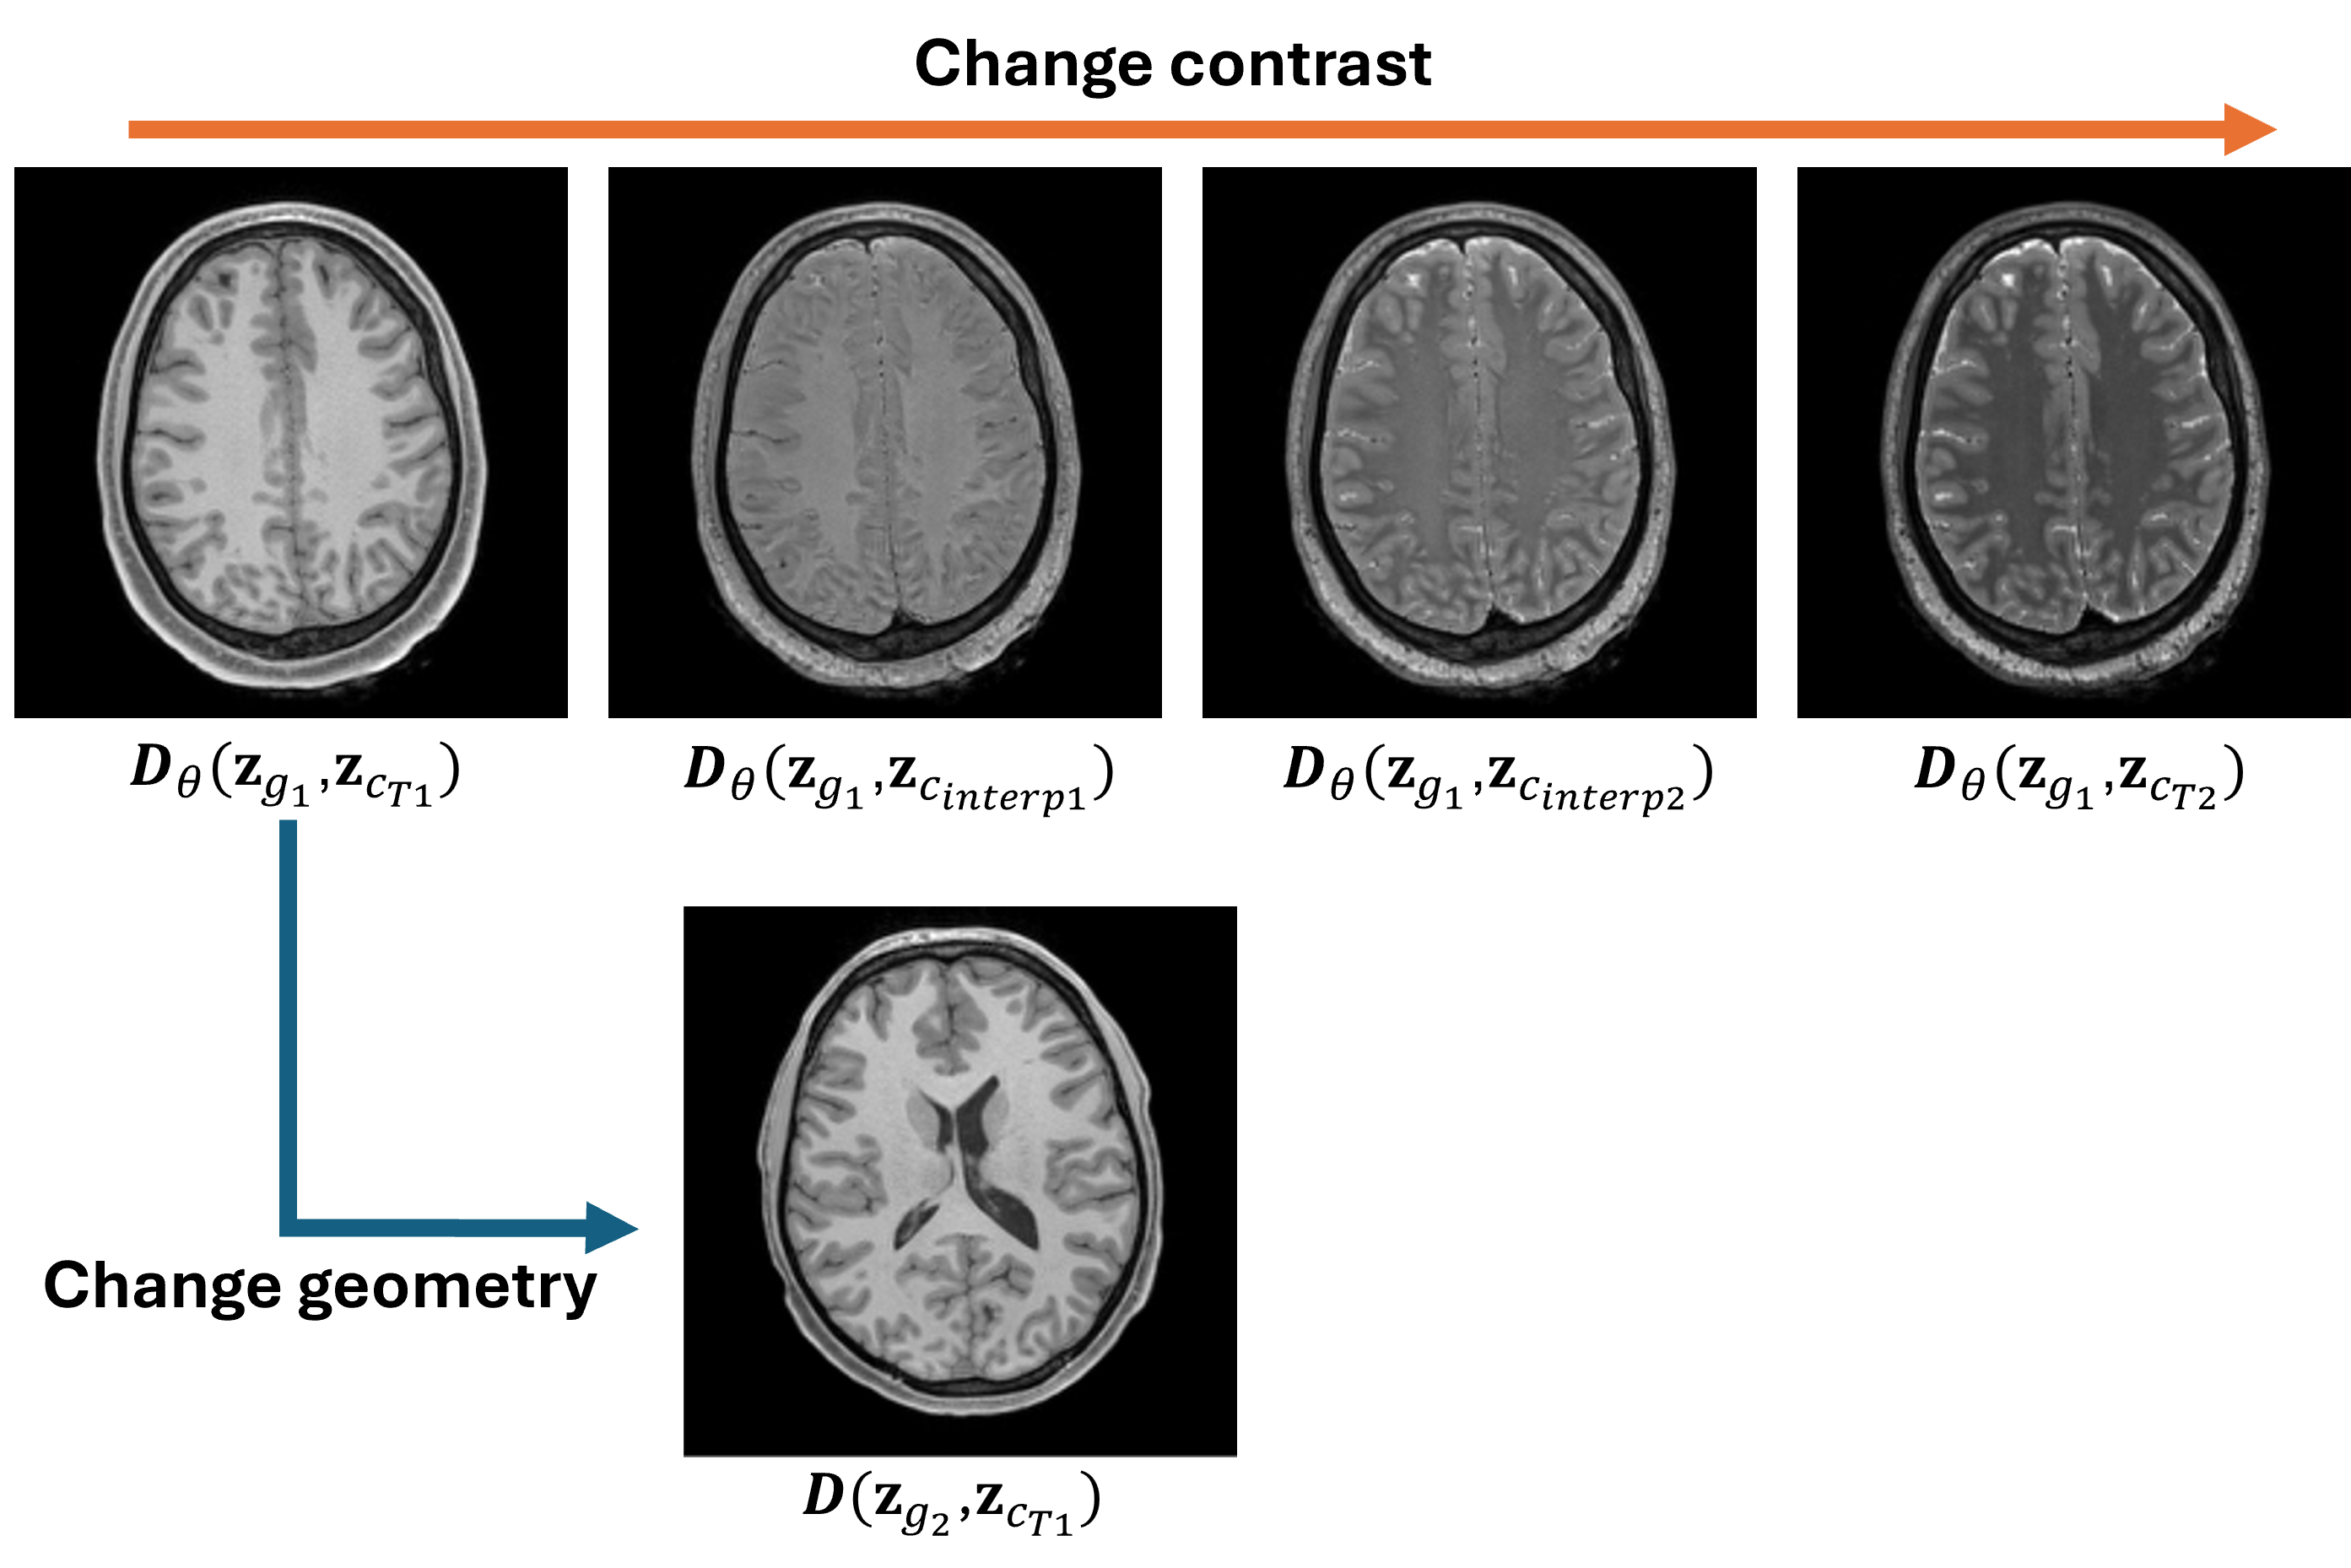

We first evaluated the feature disentanglement of the proposed representation. As shown in Fig. 3, with the geometry latents of two images with the same anatomy fixed, interpolating between their respective contrast latents generated images with varying contrasts but identical anatomy, demonstrating effective separation of geometric and contrast features. These results also support that images with different contrast weightings can be produced by combining a shared geometry latent with varying contrast latents, a strong constraint for multicontrast image reconstruction.

This disentanglement property directly motivates the application of our learned representation to MR parameter mapping, where sequences of images with varying contrasts are reconstructed and quantified. In this work, we evaluated the utility of the proposed representation and image reconstruction using quantitative $`\text{T}_1`$ and $`\text{T}_2`$ mapping tasks.